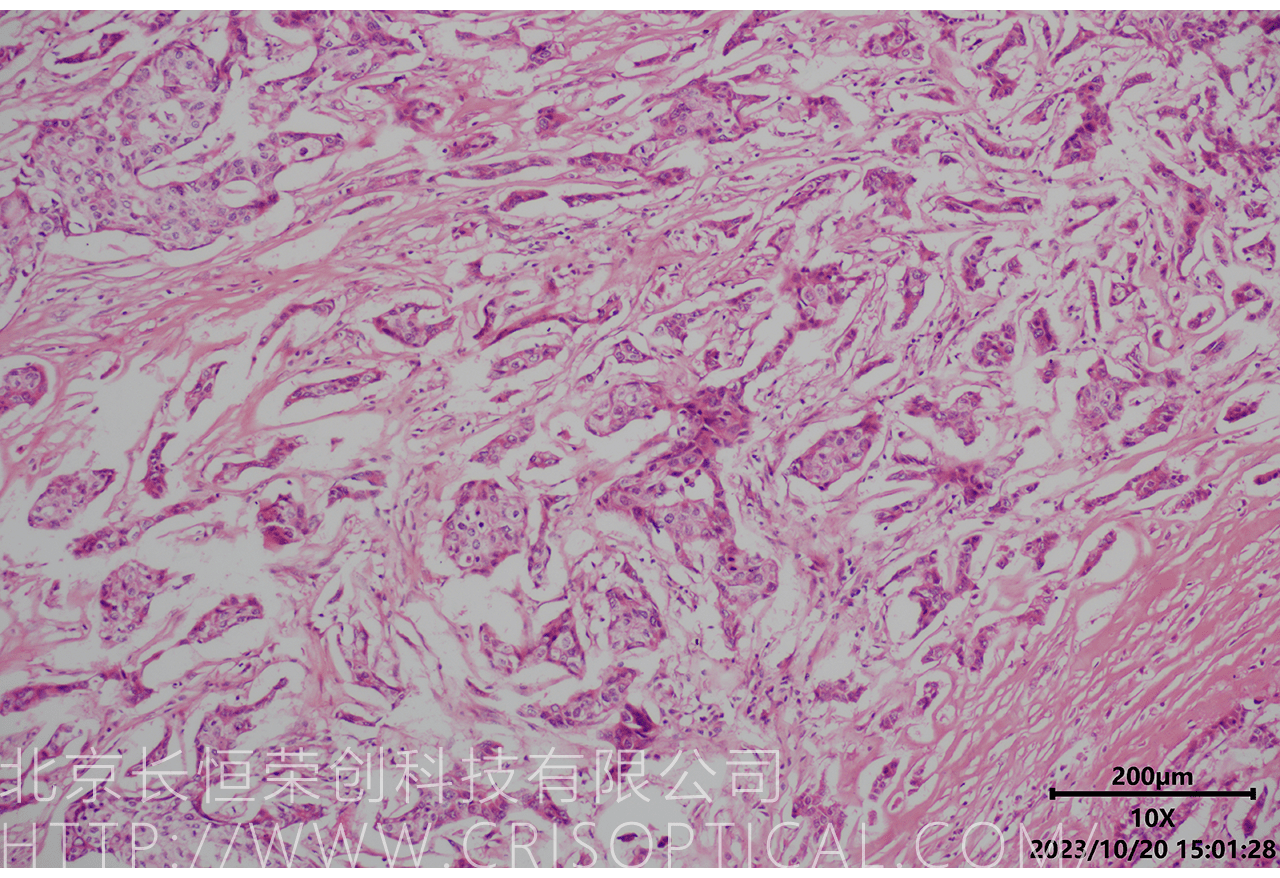

腫瘤診斷:對癌癥和其他腫瘤的病理切片觀察是確定腫瘤類型、分級和分期的關鍵步驟。醫(yī)生通過觀察組織樣本中的細胞形態(tài)、核形狀、分裂活性和其他特征,可以識別腫瘤的類型,幫助決定治療方法。